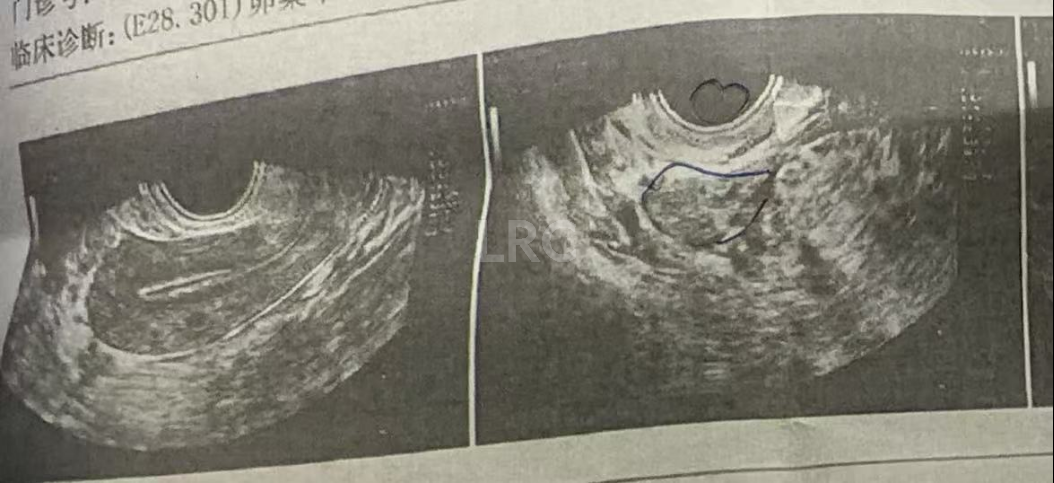

促排第十天

阴超检查:

- 右侧卵泡 2 颗 (20,15mm)

- 左侧卵泡 2 颗 (23,7mm)

治疗结果

取卵及受精

取卵:3颗

成熟MII:3颗

ICSI受精:2颗

养囊成功:2颗